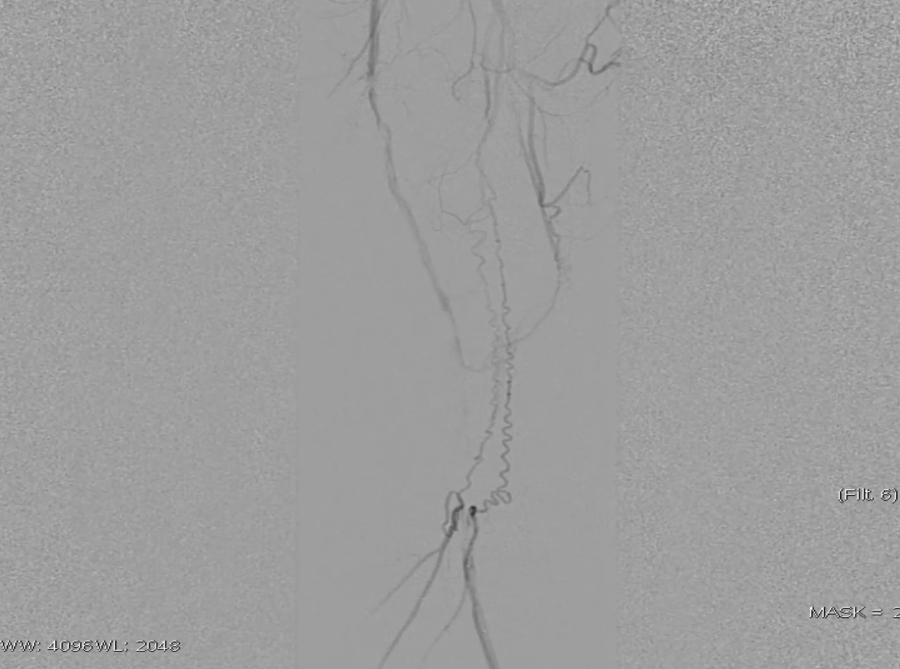

操作要点:在路径图引导下,使用超滑导丝配合6F导管选择进入支架近端(避免导丝从支架网眼穿出),随后采用新型超声开通导管尝试开通病变段。

器械优势:超声导管头端可发射超声波,能轻松通过坚硬闭塞部分;

注意事项:该导管硬度较大、方向选择性差,需配合V18导丝引导,推进时需缓慢操作并密切关注患者疼痛等不良反应。

调整与确认:开通至股浅动脉中段后,发现导丝向另一个方向打弯,退回后重新选择路径,最终顺利送至股浅动脉远端真腔,造影证实开通成功。